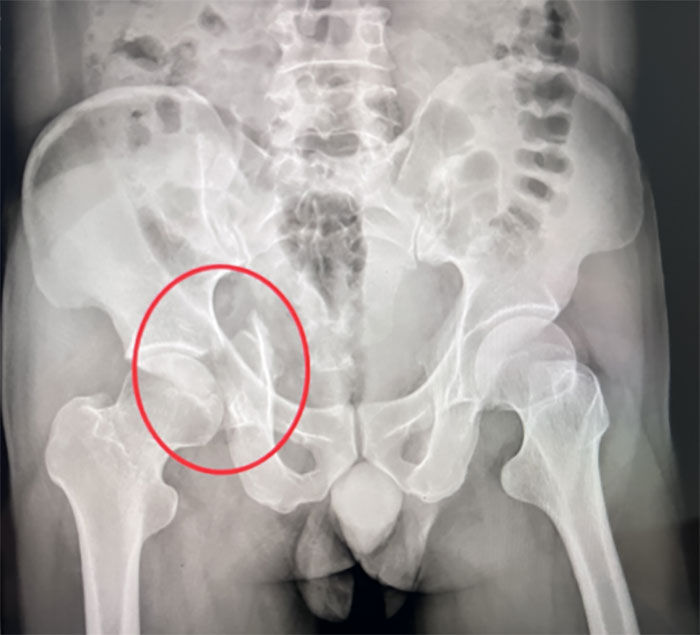

骨折部位

由于骨盆本身解剖位置就比較復雜,再加上患者傷情嚴重,使得手術難度增加。在此情況下,創(chuàng)傷骨二科(骨八科)團隊對許女士的病情進行了詳細討論,決定通過3D打印技術協(xié)作完成手術。創(chuàng)傷骨二科(骨八科)團隊對許女士的影像數(shù)據(jù)進行三維重建,制作出一個真實復原患者骨盆的立體模型,幫助團隊全面精準地了解骨盆的結構和骨折情況。